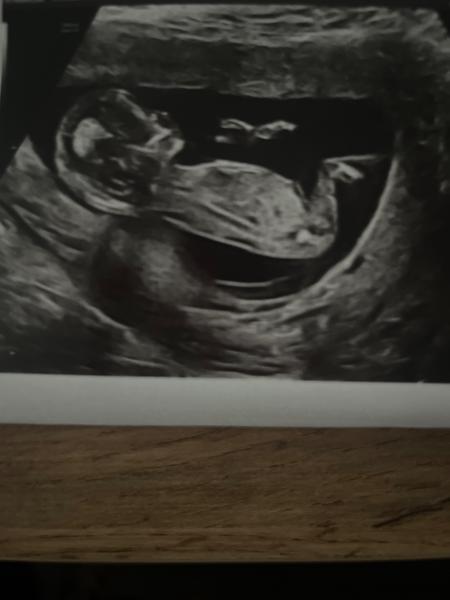

@kendra73 aj ja sa pridám čo myslite ?